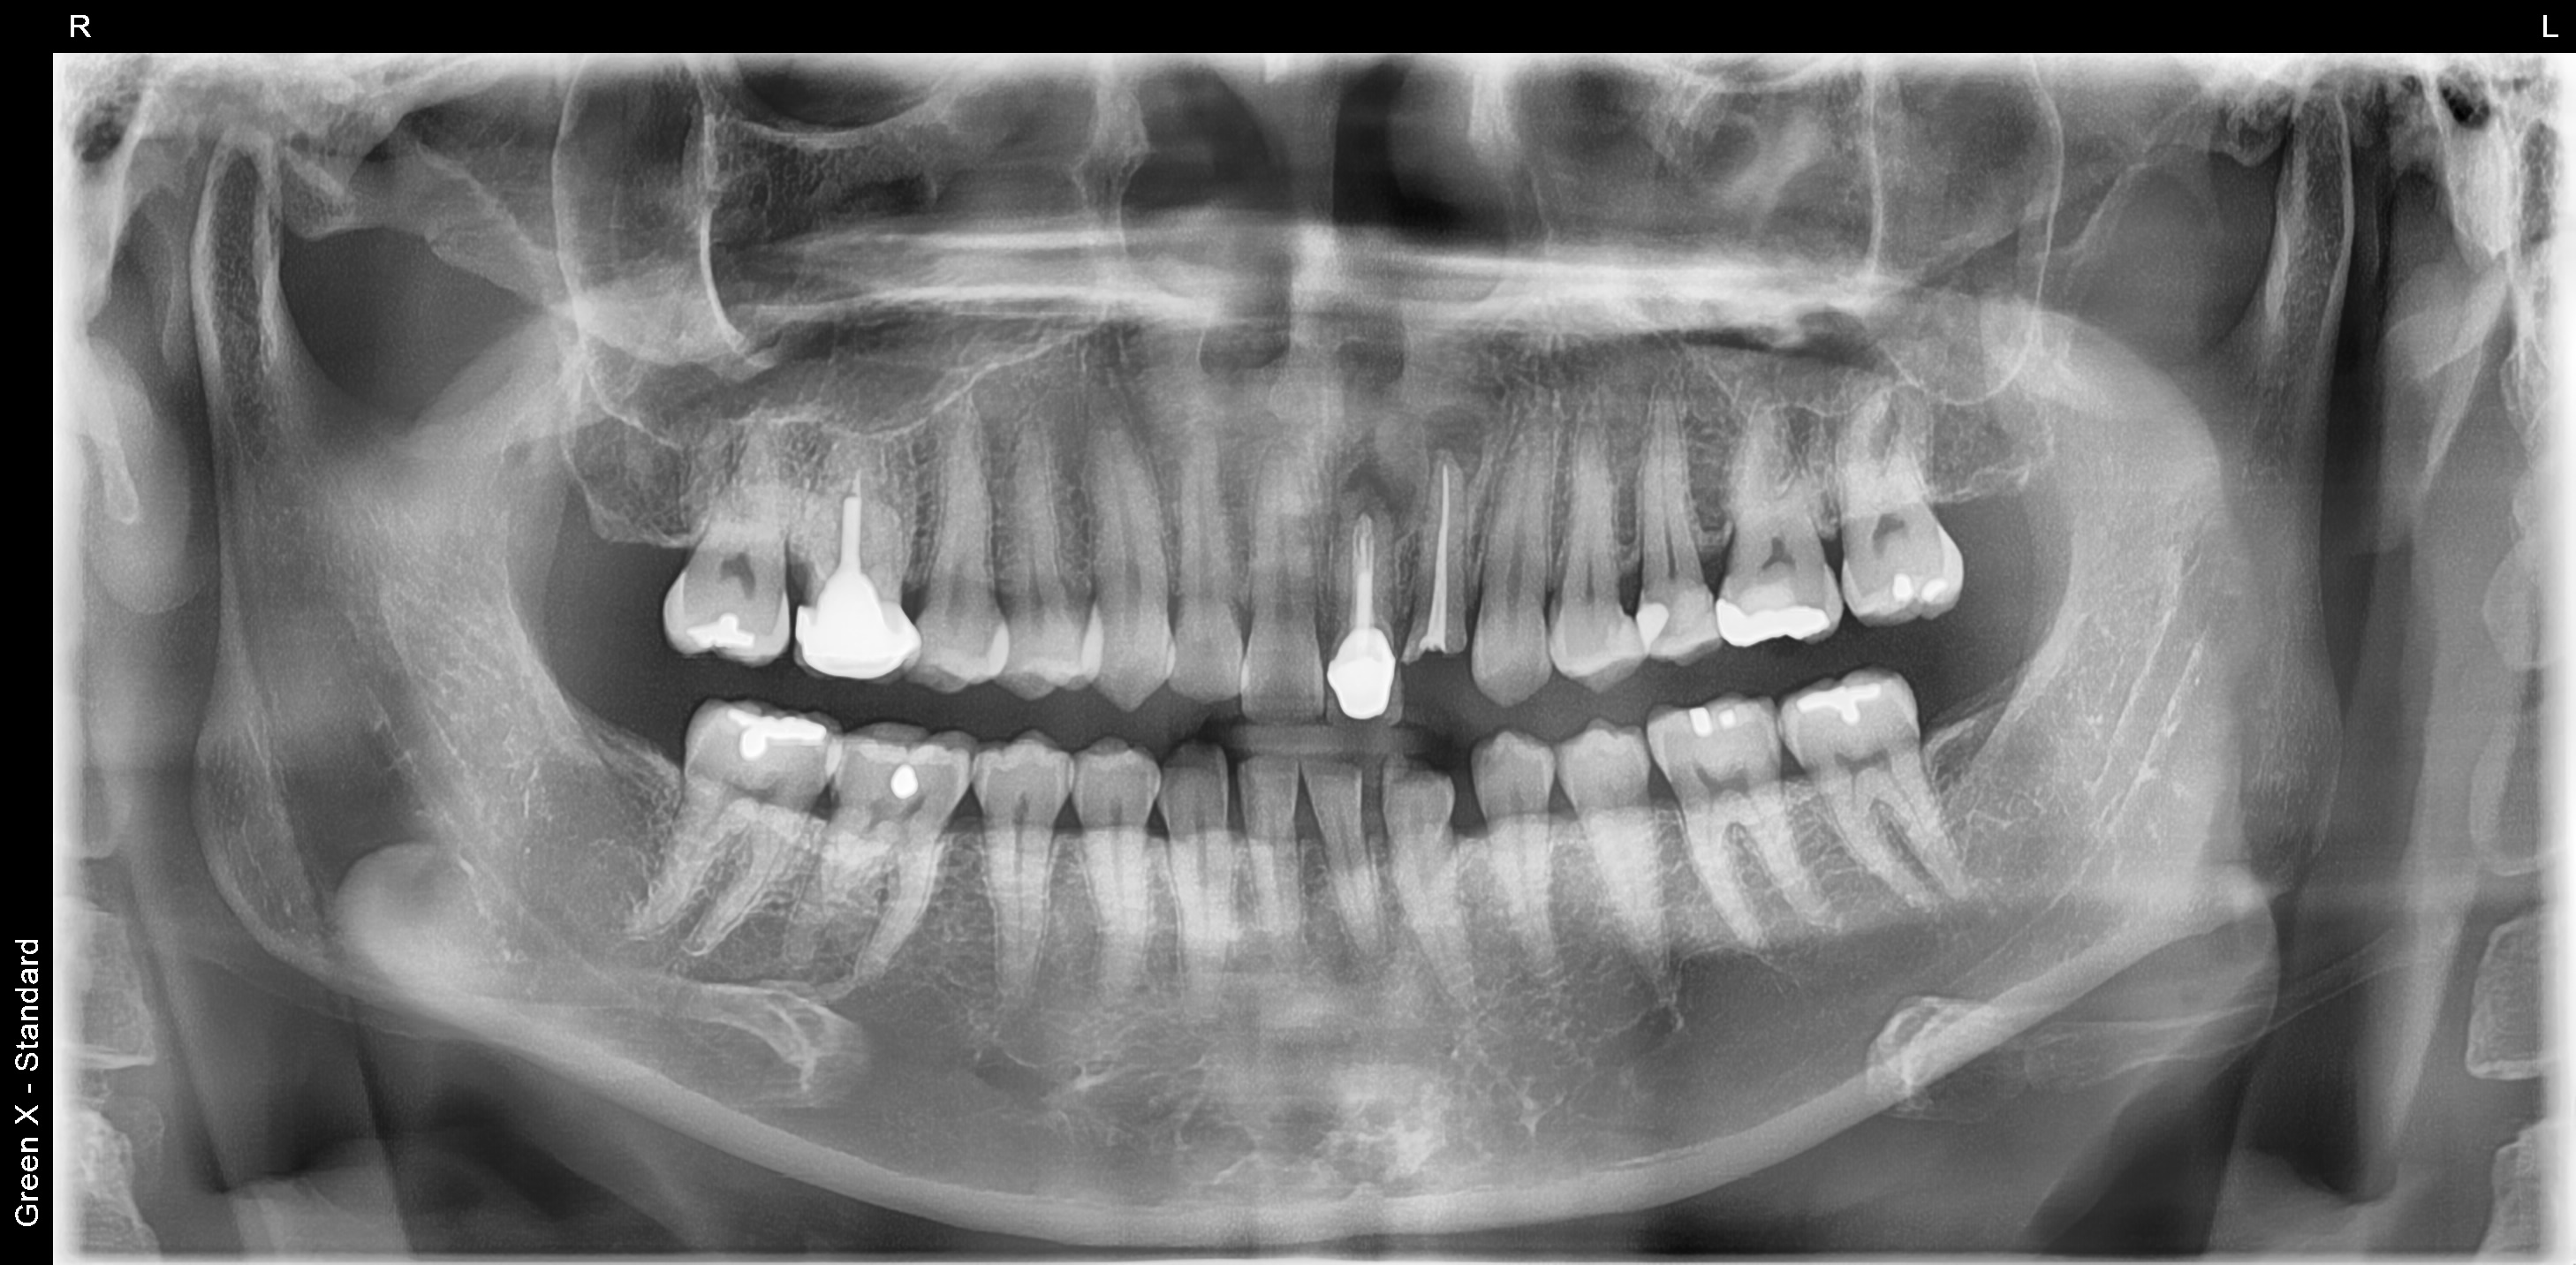

3개월 이후 잇몸뼈가 재생이된 것을 확인하고 임플란트 식립를 식립하였습니다.

다시 3개월 후 보철을 완성해 드렸습니다.